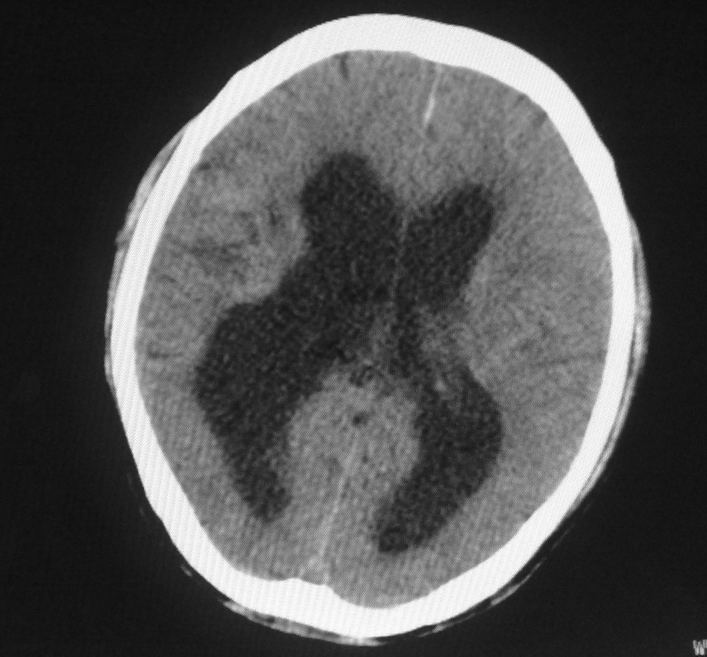

标题: CT24862:男,61岁,发热,有脑出血病史。 [打印本页]

男,61岁,发热,有脑出血病史。

脑积水!四脑室显示不清,导水管梗阻?建议mri!

右侧基底节及放射冠软化灶,脑积水,四脑室显示不清,导水管梗阻?建议mri!

梗阻性脑积水,出血后粘连所致

1)右侧基底节区、右侧放射冠及右侧丘脑软化灶。2)脑积水。